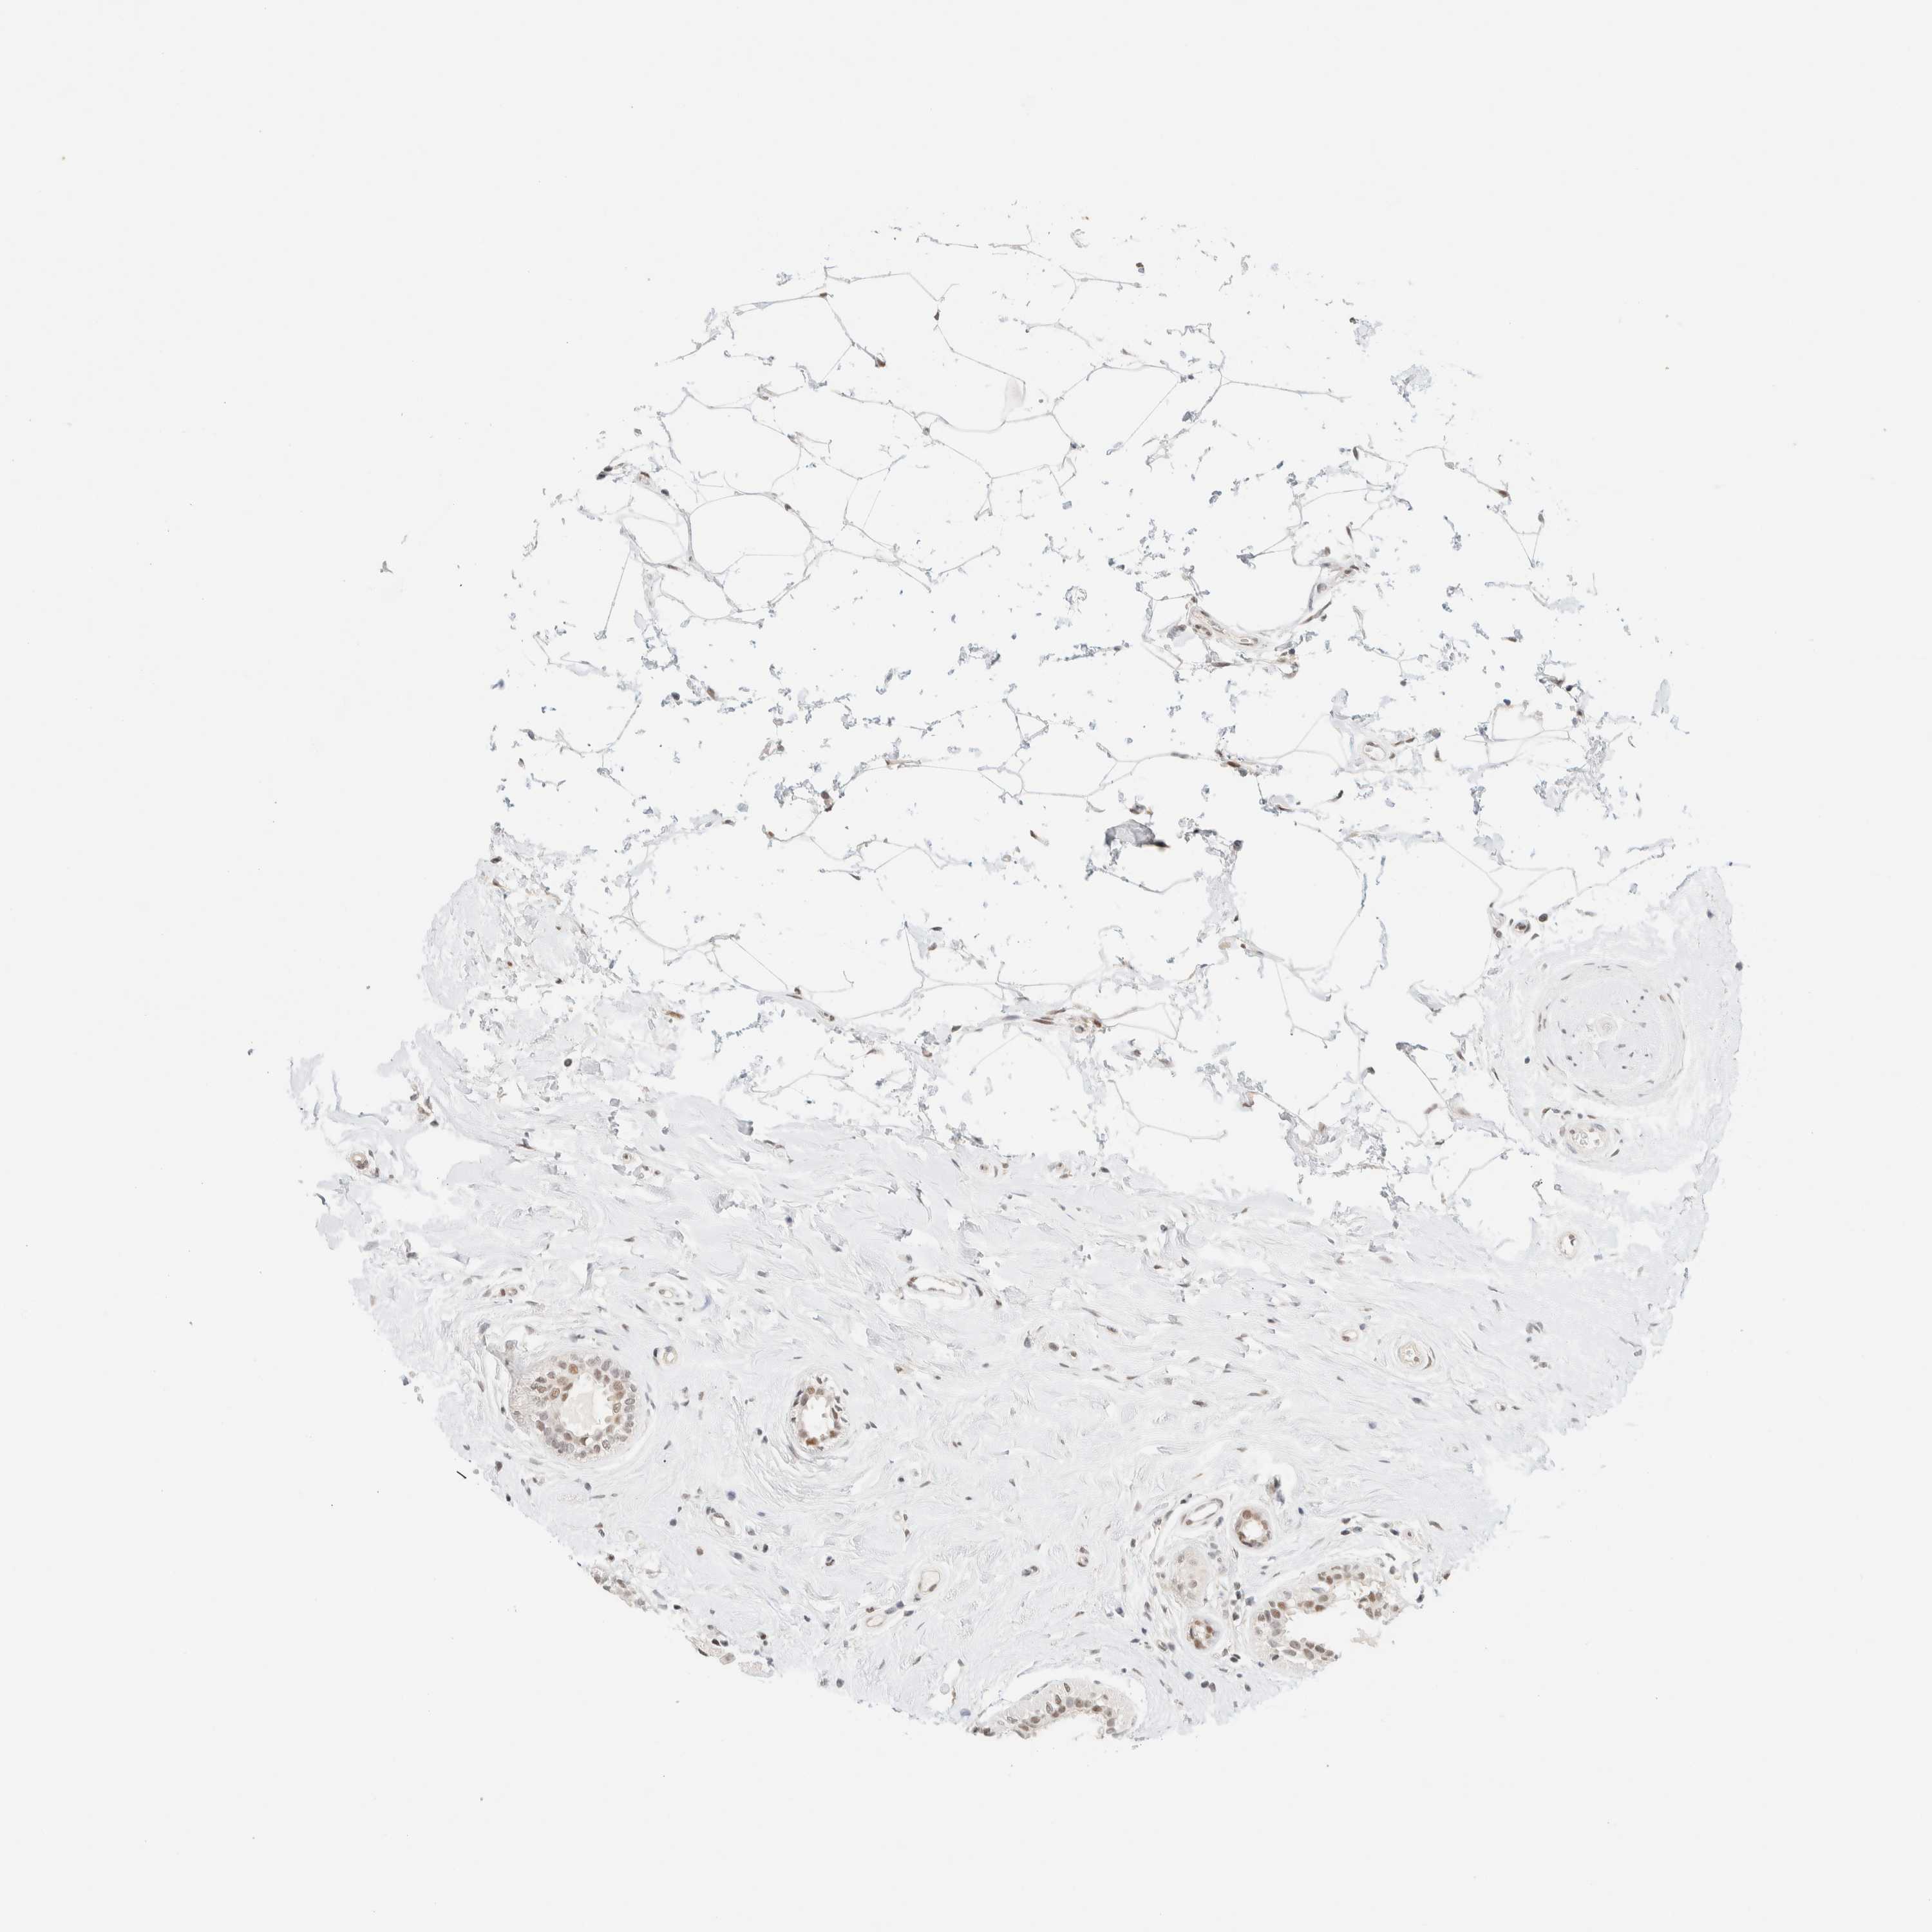

BRCA TCGA BRCA VALIDATION PROTEIN EXPRESSION

ANTIBODIES

AND

VALIDATION